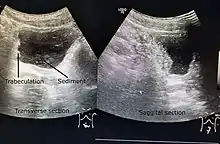

A paraplegic patient with neurogenic bladder on regular ultrasound follow-up showing thickened bladder wall with trabecculations and sediments within the bladder.

Ultrasound imaging can give information on the shape of the bladder, post-void residual volume, and evidence of kidney damage such as kidney size, thickness or ureteral dilation.[5] Trabeculated bladder on ultrasound indicates high risk of developing urinary tract abnormalities such as hydronephrosis and stones.[6] A voiding cystourethrography study uses contrast dye to obtain images of the bladder both when it is full and after urination which can show changes in bladder shape consistent with neurogenic bladder.[5]